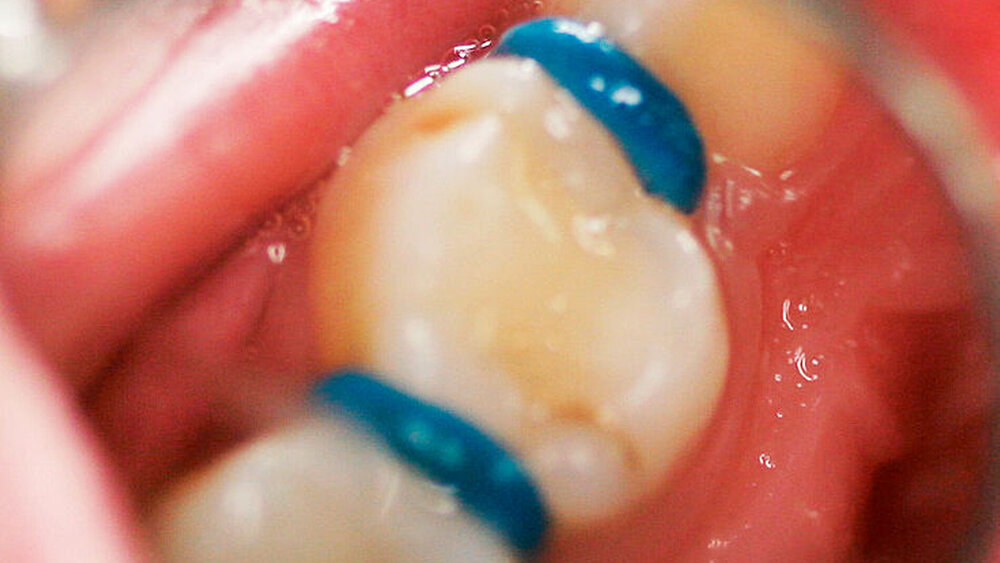

Generell existiert eine konsistente Evidenz, welche die Effektivität von SDF bei der Inaktivierung von koronaler Karies im Milchgebiss und bei der Arretierung und Prävention von Wurzelkaries bei Senioren belegt [Seifo et al., 2019; Chibinski et al., 2017). In Deutschland enthält das einzige verfügbare Produkt Silber-Fluorid-Ammoniak und Kalium-Jodid (Riva-Star®, SDI Dental Limited). Dieses Produkt wird allerdings in Europa im Unterschied zu Asien und Australien bis jetzt hauptsächlich als Desensibilisierungsmittel bei überempfindlichen Zähnen angewandt. Für die Kariestherapie ist die Nutzung von Silberprodukten hierzulande ein „Off-Label-Use“, aber trotzdem sicher und effektiv. Die Behandlung eines Patienten mittels SDF ist in den Abbildungen 1a und 1b dargestellt.

Bei der Hall-Technik (HT) handelt es sich um eine minimal-invasive Behandlung für kariöse Milchmolaren, bei der im Gegensatz zur konventionellen Stahlkronenversorgung keine Lokalanästhesie, keine Präparation und keine Kariesentfernung erfolgt, sondern lediglich eine vorgefertigte Stahlkrone auf einen für diese Technik geeigneten kariösen, pulpal asymptomatischen Milchmolaren zementiert wird [Santamaria et al., 2018; Innes et al., 2007). Bei sehr engen Approximalkontakten kann nach einer Zahnseparation mittels orthodontischer Separiergummis in der Regel eine Stahlkronenversorgung in der Hall-Technik sehr leicht durchgeführt werden. Die der Standardfüllung überlegenen Erfolgsraten der Hall-Technik (2-Jahres-Erfolgsraten 90-100 Prozent versus circa 50-80 Prozent bei Füllungen) sind mit einem hohen Evidenzgrad in der vorliegenden wissenschaftlichen Literatur belegt [Innes et al., 2007; Santamaria et al., 2020; Innes et al., 2015]. Die Behandlung eines Patienten mittels Hall-Technik ist in den Abbildungen 2a bis 2c dargestellt. Einen Hinweise auf weiterführende Literatur dazu finden Sie am Ende des Beitrags.